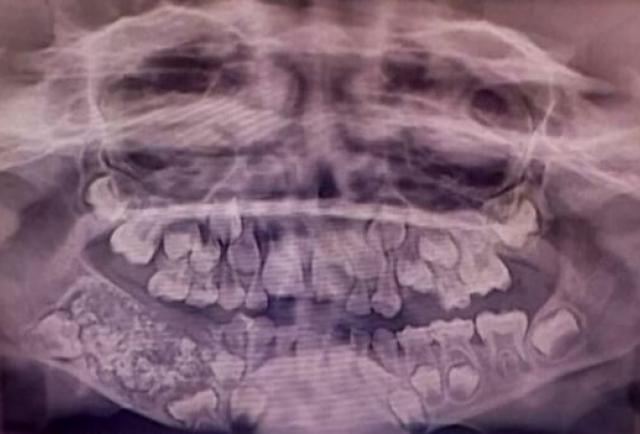

Luego de varios exámenes y diagnósticos, los odontólogos descubrieron una estructura grande y dura, de alrededor 200 gramos. Al retirarla notaron que tenía adentro 526 dientes, cuyas dimensiones iban desde 1 hasta 15 milímetros.

Para los médicos, el niño habría presentado hinchazón en la mandíbula por varios años. Al realizarle una radiografía y tomografía hallaron una estructura con forma de bolsa, conocida como odontoma compuesto.